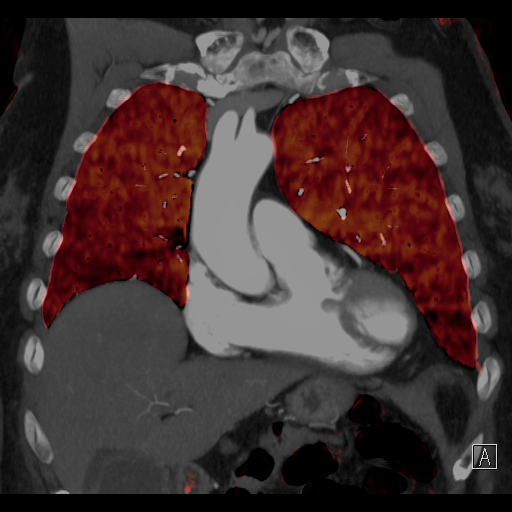

脱水や長時間同じ姿勢を取ることなどで脚の静脈の流れが悪くなり、血栓ができることがあります。その血栓が肺に運ばれて肺動脈を詰まらせてしまうのが肺血栓塞栓症です。CTを用いることで肺動脈内の血栓を造影欠損像として直接描出できます。さらに、デュアルエナジー撮影法を利用すると肺血流の機能情報を可視化することができます。

デュアルエナジーイメージングによる肺灌流評価CT(治療前と抗凝固薬服用後)